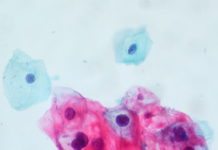

Tonsillar Crypts Might Shield HPV, Giving Way to Cancer

The pathogenesis of human papillomavirus (HPV)-associated oropharyngeal squamous cell carcinoma is currently an important topic of...